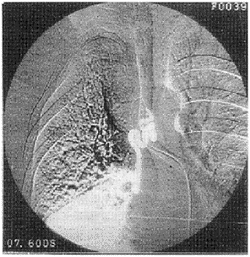

原發氣管支氣管腫瘤X射線圖1.各種氣管良性腫瘤的特點

1.X 線檢查 氣管的後前位及側位體層像、氣管分叉體層像對診斷氣管、支氣管腫瘤有重要意義。這些檢查可清晰地顯示氣管腔內腫瘤的輪廓、位置、範圍和病變與鄰近器官的關係。良性腫瘤可有鈣化,基底有細蒂。惡性腫瘤基底寬,邊界、輪廓均不完整。行後前位氣管體層像時,囑病人說“E”,可以很好地顯示後前方向的喉部以及氣管全長的詳情;照側位氣管像時做吞咽動作,能使喉部抬高,從而清晰地顯示喉與氣管的關係;左、右後斜位氣管體層像對顯示器官,尤其是支氣管各主要分支的病變有很大幫助。

2.CT 檢查 對氣管腫瘤的診斷有很大幫助。CT 可顯示氣管腔內的密度增高的軟組織影,多為偏心性,氣管壁增厚,氣管呈不規則狹窄,大約10%的氣管腫瘤沿氣管周圍生長,30%~40%的氣管腫瘤直接累及縱隔。支氣管腫瘤在CT 上可表現為向腔內生長或向腔外浸潤,引起支氣管不全或完全梗阻,出現阻塞性肺炎或肺不張,根據支氣管腫瘤的浸潤程度,Naidich 等將其分為6 種表現:①支氣管壁顯示正常;②支氣管壁均勻狹窄;③支氣管不規則狹窄;④支氣管腔完全阻塞;⑤支氣管腔內腫塊;⑥支氣管受壓移位。